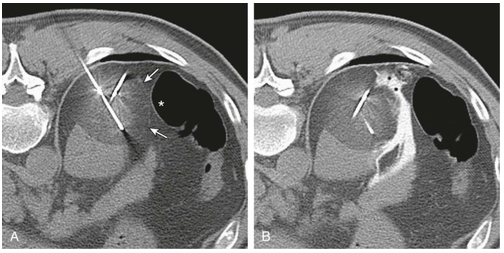

Hình 2. ccRCC đã xâm lấn mạc Gerotta (pT4)

Hình 3. ccRCC có màu vàng, giới hạn ở thận (pT1b)

Đại thể

Thường là khối u vỏ thận một bên và đơn ổ, kích thước trung bình khoảng 7 cm. Khối u thường có ranh giới rõ, được bao quanh bởi giả bao u, phát triển theo kiểu đẩy nở và lồi ra từ vỏ thận. Hình thái đại thể đa dạng với thành phần đặc và nang, kèm các vùng xơ hóa màu xám và các ổ xuất huyết mới hoặc cũ màu nâu; hoại tử và biến đổi nang gặp thường xuyên. Khối u có màu vàng ánh kim do hàm lượng lipid cao; các khối u có độ mô học cao hơn có thể không có màu vàng do hàm lượng lipid và glycogen thấp hơn. Các vùng mềm, dạng thịt có thể phản ánh sự hiện diện của biệt hóa dạng sarcomatoid. Thường xuyên ghi nhận xâm lấn tĩnh mạch thận và xoang thận. Tổn thương hai bên và đa ổ là đặc điểm gợi ý bệnh lý di truyền.

Về phân giai đoạn, các khối u có kích thước lớn hơn 7 cm hầu như luôn xâm lấn mỡ xoang thận; nếu không quan sát thấy xâm lấn ở các khối u lớn, cần tiến hành xem xét lại đại thể bổ sung. Xâm lấn bao thận được đặc trưng bởi sự tiến triển không đều và gián đoạn của khối u vào mô mỡ quanh thận kèm theo mất đường viền ngoài lồi đều, nhẵn của thận; khối u lồi đều, nhẵn và được bao phủ bởi giả bao ung thư không được xem là xâm lấn mỡ quanh thận. Để chẩn đoán xâm lấn, tế bào u phải tiếp xúc trực tiếp với mô mỡ hoặc xâm nhập dạng các lưỡi không đều vào mô quanh thận, có hoặc không kèm phản ứng xơ sinh. Xâm lấn xoang thận là con đường lan tràn ngoài thận thường gặp nhất và thường xảy ra trước xâm lấn bao thận; khác với bao thận,xoang thận không được ngăn cách với nhu mô thận bằng một bao xơ riêng biệt. Không được coi là xâm lấn thực sự nếu khối u vẫn được ngăn cách với các cấu trúc xoang bởi một viền nhu mô thận; được coi là xâm lấn xoang thận khi khối u lồi rõ vào mô mỡ xoang thận vượt quá nhu mô thận, kể cả khi vẫn được bao phủ bởi mô liên kết thưa. Việc khối u bao quanh các cấu trúc mạch máu hoặc bạch mạch lớn là dấu hiệu gợi ý xâm lấn mỡ xoang thận. Xâm lấn mạch máu có thể biểu hiện dưới dạng các nốt u trong xoang thận; trong trường hợp lòng mạch bị bít một phần, sự hiện diện của một lớp nội mô đơn độc phủ lên bề mặt khối u không loại trừ xâm lấn mạch máu. Xâm lấn tĩnh mạch nhỏ thường hàm ý xâm lấn tĩnh mạch lớn, và xâm lấn xoang thận thường đồng nghĩa với xâm lấn tĩnh mạch thận, do đó cần được thăm khám và đánh giá một cách thận trọng.